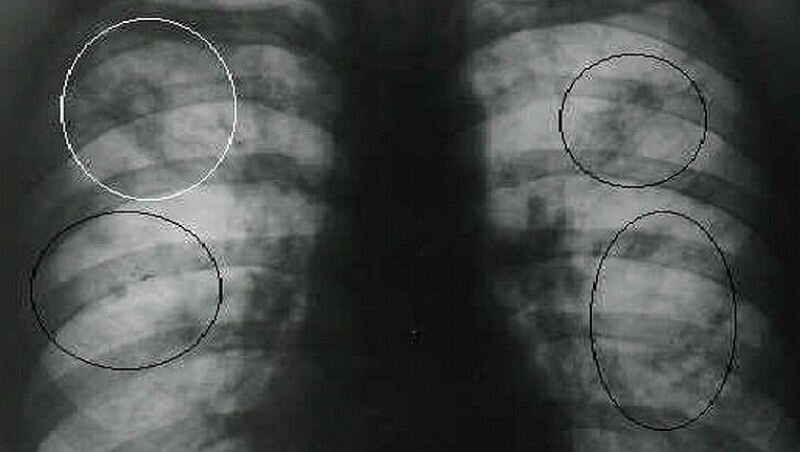

фото: Moydiagnos.ru